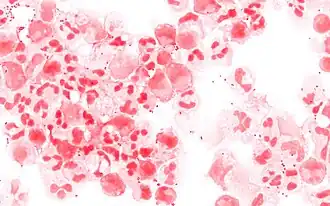

Résultats (galeries de photos)

- Exemples de micro-organismes à Gram positif

Streptocoques sur fond de PNN Gram –